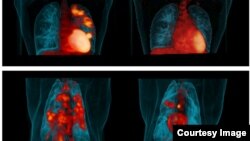

Representative human PET/CT before LZD therapy (top, left) and after 6 months of LZD therapy (top, right). PET/CT of a cynomolgus macaque before receiving LZD therapy (bottom, left) and after 2 months of LZD therapy (bottom, right). Credit: JoAnne Flynn, Teresa Coleman, Clifton Barry III.

Borrowing from techniques used by cancer-drug researchers, Barry and his team used two advanced imaging techniques, PET and CT scans, that can look into the body of people participating in drug trials and see - literally see - whether a particular treatment being tested is working against the tuberculosis infection.